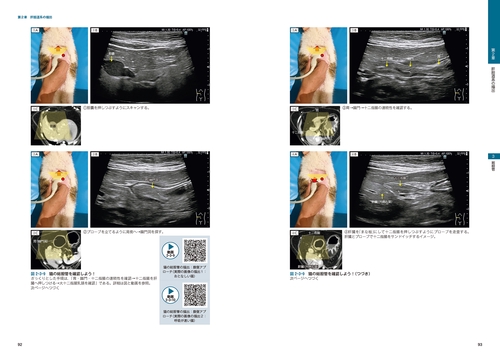

画像とシェーマで学ぶ犬と猫の超音波 Vol.3 腹部 下巻 | 臨床獣医学。犬と猫の超音波 下腹部 vol.03 裁断済み 【公式通販】。画像とシェーマで学ぶ犬と猫の超音波 Vol.3 腹部 下巻 | 臨床獣医学。犬と猫の超音波に関する詳細な学習資料。- タイトル: 犬と猫の超音波ご覧いただきありがとうございます。。ビジュアルと動画でわかる! 犬と猫の腹部超音波の描出レッスン 上巻。

• 画像とシェーマで学ぶ犬と猫の超音波 Vol.3 腹部 下巻 | 臨床獣医学

• ビジュアルと動画でわかる! 犬と猫の腹部超音波の描出レッスン 上巻